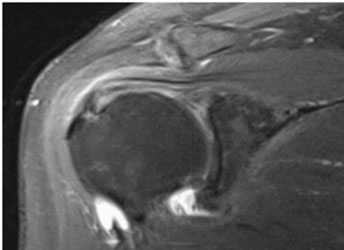

Наиболее информативными являются инструментальные методы исследования. Рентгенография используется редко, поскольку этот метод позволяет оценить лишь состояние костной ткани, а о повреждении связочного аппарата с ее помощью можно судить косвенно. КТ и МРТ позволяют комплексно оценить состояние плечелопаточного сочленения, определить состояние мягких тканей, расстояние между костными структурами. Эти методы позволяют не только выявить болезнь, но и определить оптимальную тактику лечения.

Импинджмент-синдром.а. МРТ плечевого сустава, б. рентгенография плечевого сустава.

- МРТ плечевого сустава. Назначается для подробного изучения мягкотканных структур: вращательной манжеты, сухожилия двуглавой мышцы, суставной губы. Обнаруживает даже незначительные дефекты (надрывы) признаки дегенерации и воспалительного процесса.